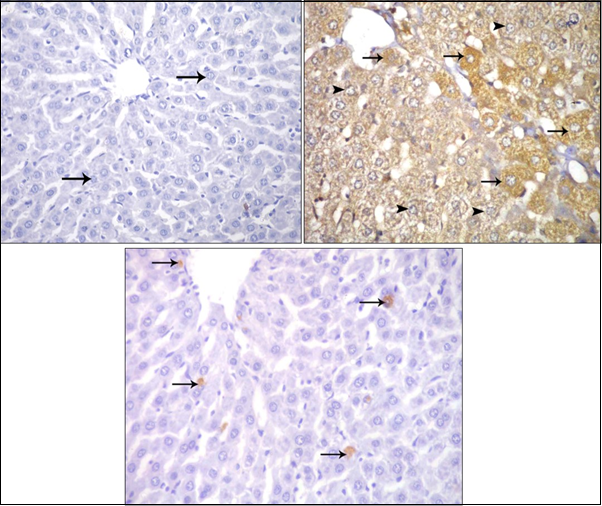

Immunohisto Chemical Staining

Immunohistochemical stained sections of the 1st and 2nd groups showed negative immune reaction for caspase 3 inside the cytoplasm of hepatocytes (Figure 11a); while strong positive reaction for Caspase 3 were noticed in the 3rd group (Figure 11b); and in the 4th group the intensity of reaction was apparently decreased (Figure 11c).

Figure 11.Photomicrographs of sections in the liver: (a) Control adult albino rat showing negative immune reaction for caspase 3 inside the cytoplasm of hepatocytes (arrow). (b) ZnONPs-treated adult albino rat showing strong positive immune reaction for caspase 3 inside the cytoplasm of hepatocytes. (c) ZnONPs & VE-treated adult albino rat showing weak positive immune reaction for caspase 3 inside the cytoplasm of hepatocytes. (Immunoperoxidase technique for caspase 3 X 400)

The results of the present study showed a very highly significant increase (P<0.001) in the number of hepatocytes with positive immune reaction for Caspase 3 in the ZnONPs-treated group when compared with other groups (Figure 12).

Caspase 3 stained liver sections of ZnONPs- treated rats showed strong positive reactions in the cytoplasm of hepatocytes. These findings are in accordance with those of Yousef and Mohamed 41, who stated that the liver apoptosis biomarker caspase3 was significantly up-regulated in rats administered either ZnO-bulk or its NPs orally (500 mg/kg bw) for 10 successive days. These findings confirmed statistically by morphometric analysis of the number of hepatocytes with caspase 3 positive immunoreaction and area percentage of collagen fiber that showed a highly significant increase (P<0.001) in ZnONPs- treated group when compared with that of the control group. In addition, there was a non-significant difference between the control and ZnONPs+VE- treated groups, this is in accordance with Al-Rasheed et al., 13.